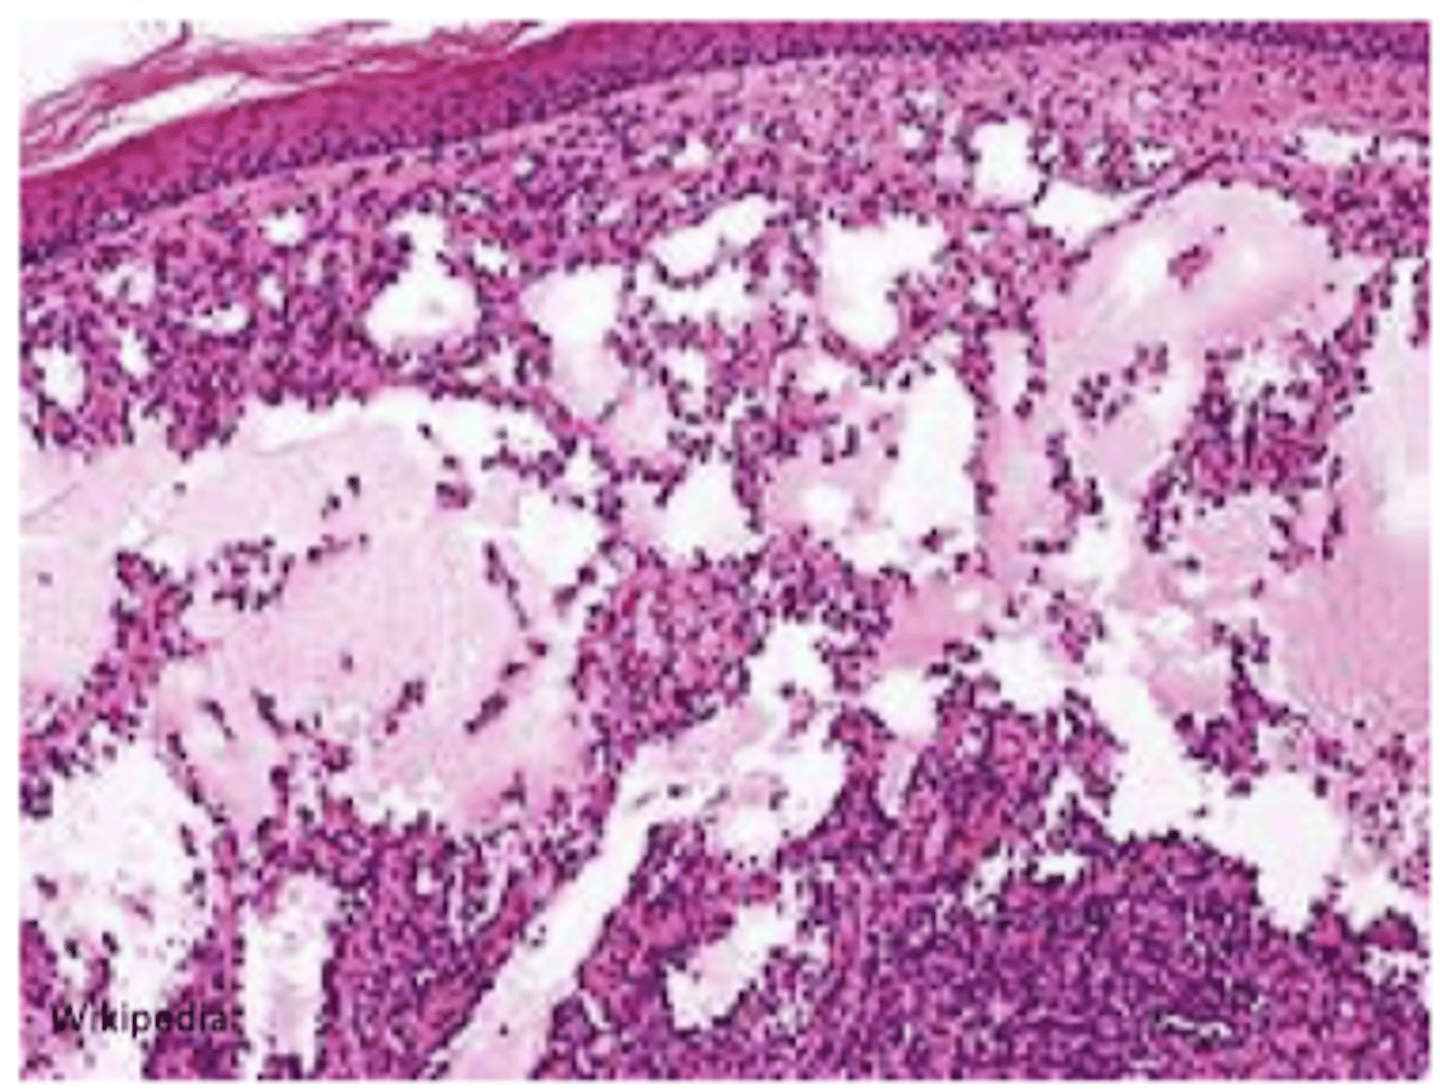

lymphangioma

benign lymphatic counterpart of hemangioma

simple lymphangioma

network of endothelium lined channels w/ no RBC's

head, neck, axilla

cavernous lymphangioma

neck or axilla of children

massively dilated spaces with CT stroma and lymphoid aggregates